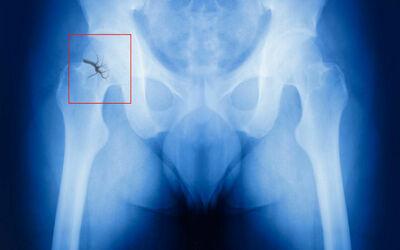

- рентген в двух проекциях;

- КТ тазобедренного сустава (помогает в тех случаях, когда другие процедуры не дают результата, например, при вколоченном переломе шейки бедра).

- остеосинтез;

- эндопротезирование.

Первый метод заключается в том, что обломки кости надежно фиксируют при помощи различных металлоконструкций: штифтов, винтов, скоб. Благодаря этому бедренная кость удерживается в нормальном положении.

КТ тазобедренного сустава является методом выбора при подозрении на вколоченный перелом шейки бедра (линия перелома не видна на рентгене), а также для оценки степени смещения, количества осколков, планирования остеосинтеза или эндопротезирования. КТ позволяет детально визуализировать костные структуры, в отличие от МРТ (МРТ лучше показывает отек костного мозга при стресс-переломе). Исследование проводится в экстренном порядке. Противопоказания: беременность (относительное). Направление дает травматолог-ортопед.